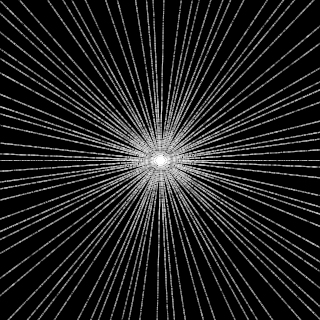

This article presents a novel undersampled magnetic resonance imaging (MRI) technique that leverages the concept of Neural Radiance Field (NeRF). With radial undersampling, the corresponding imaging problem can be reformulated into an image modeling task from sparse-view rendered data; therefore, a high dimensional MR image is obtainable from undersampled $k$-space data by taking advantage of implicit neural representation. A multi-layer perceptron, which is designed to output an image intensity from a spatial coordinate, learns the MR physics-driven rendering relation between given measurement data and desired image. Effective undersampling strategies for high-quality neural representation are investigated. The proposed method serves two benefits: (i) The learning is based fully on single undersampled $k$-space data, not a bunch of measured data and target image sets. It can be used potentially for diagnostic MR imaging, such as fetal MRI, where data acquisition is relatively rare or limited against diversity of clinical images while undersampled reconstruction is highly demanded. (ii) A reconstructed MR image is a scan-specific representation highly adaptive to the given $k$-space measurement. Numerous experiments validate the feasibility and capability of the proposed approach.